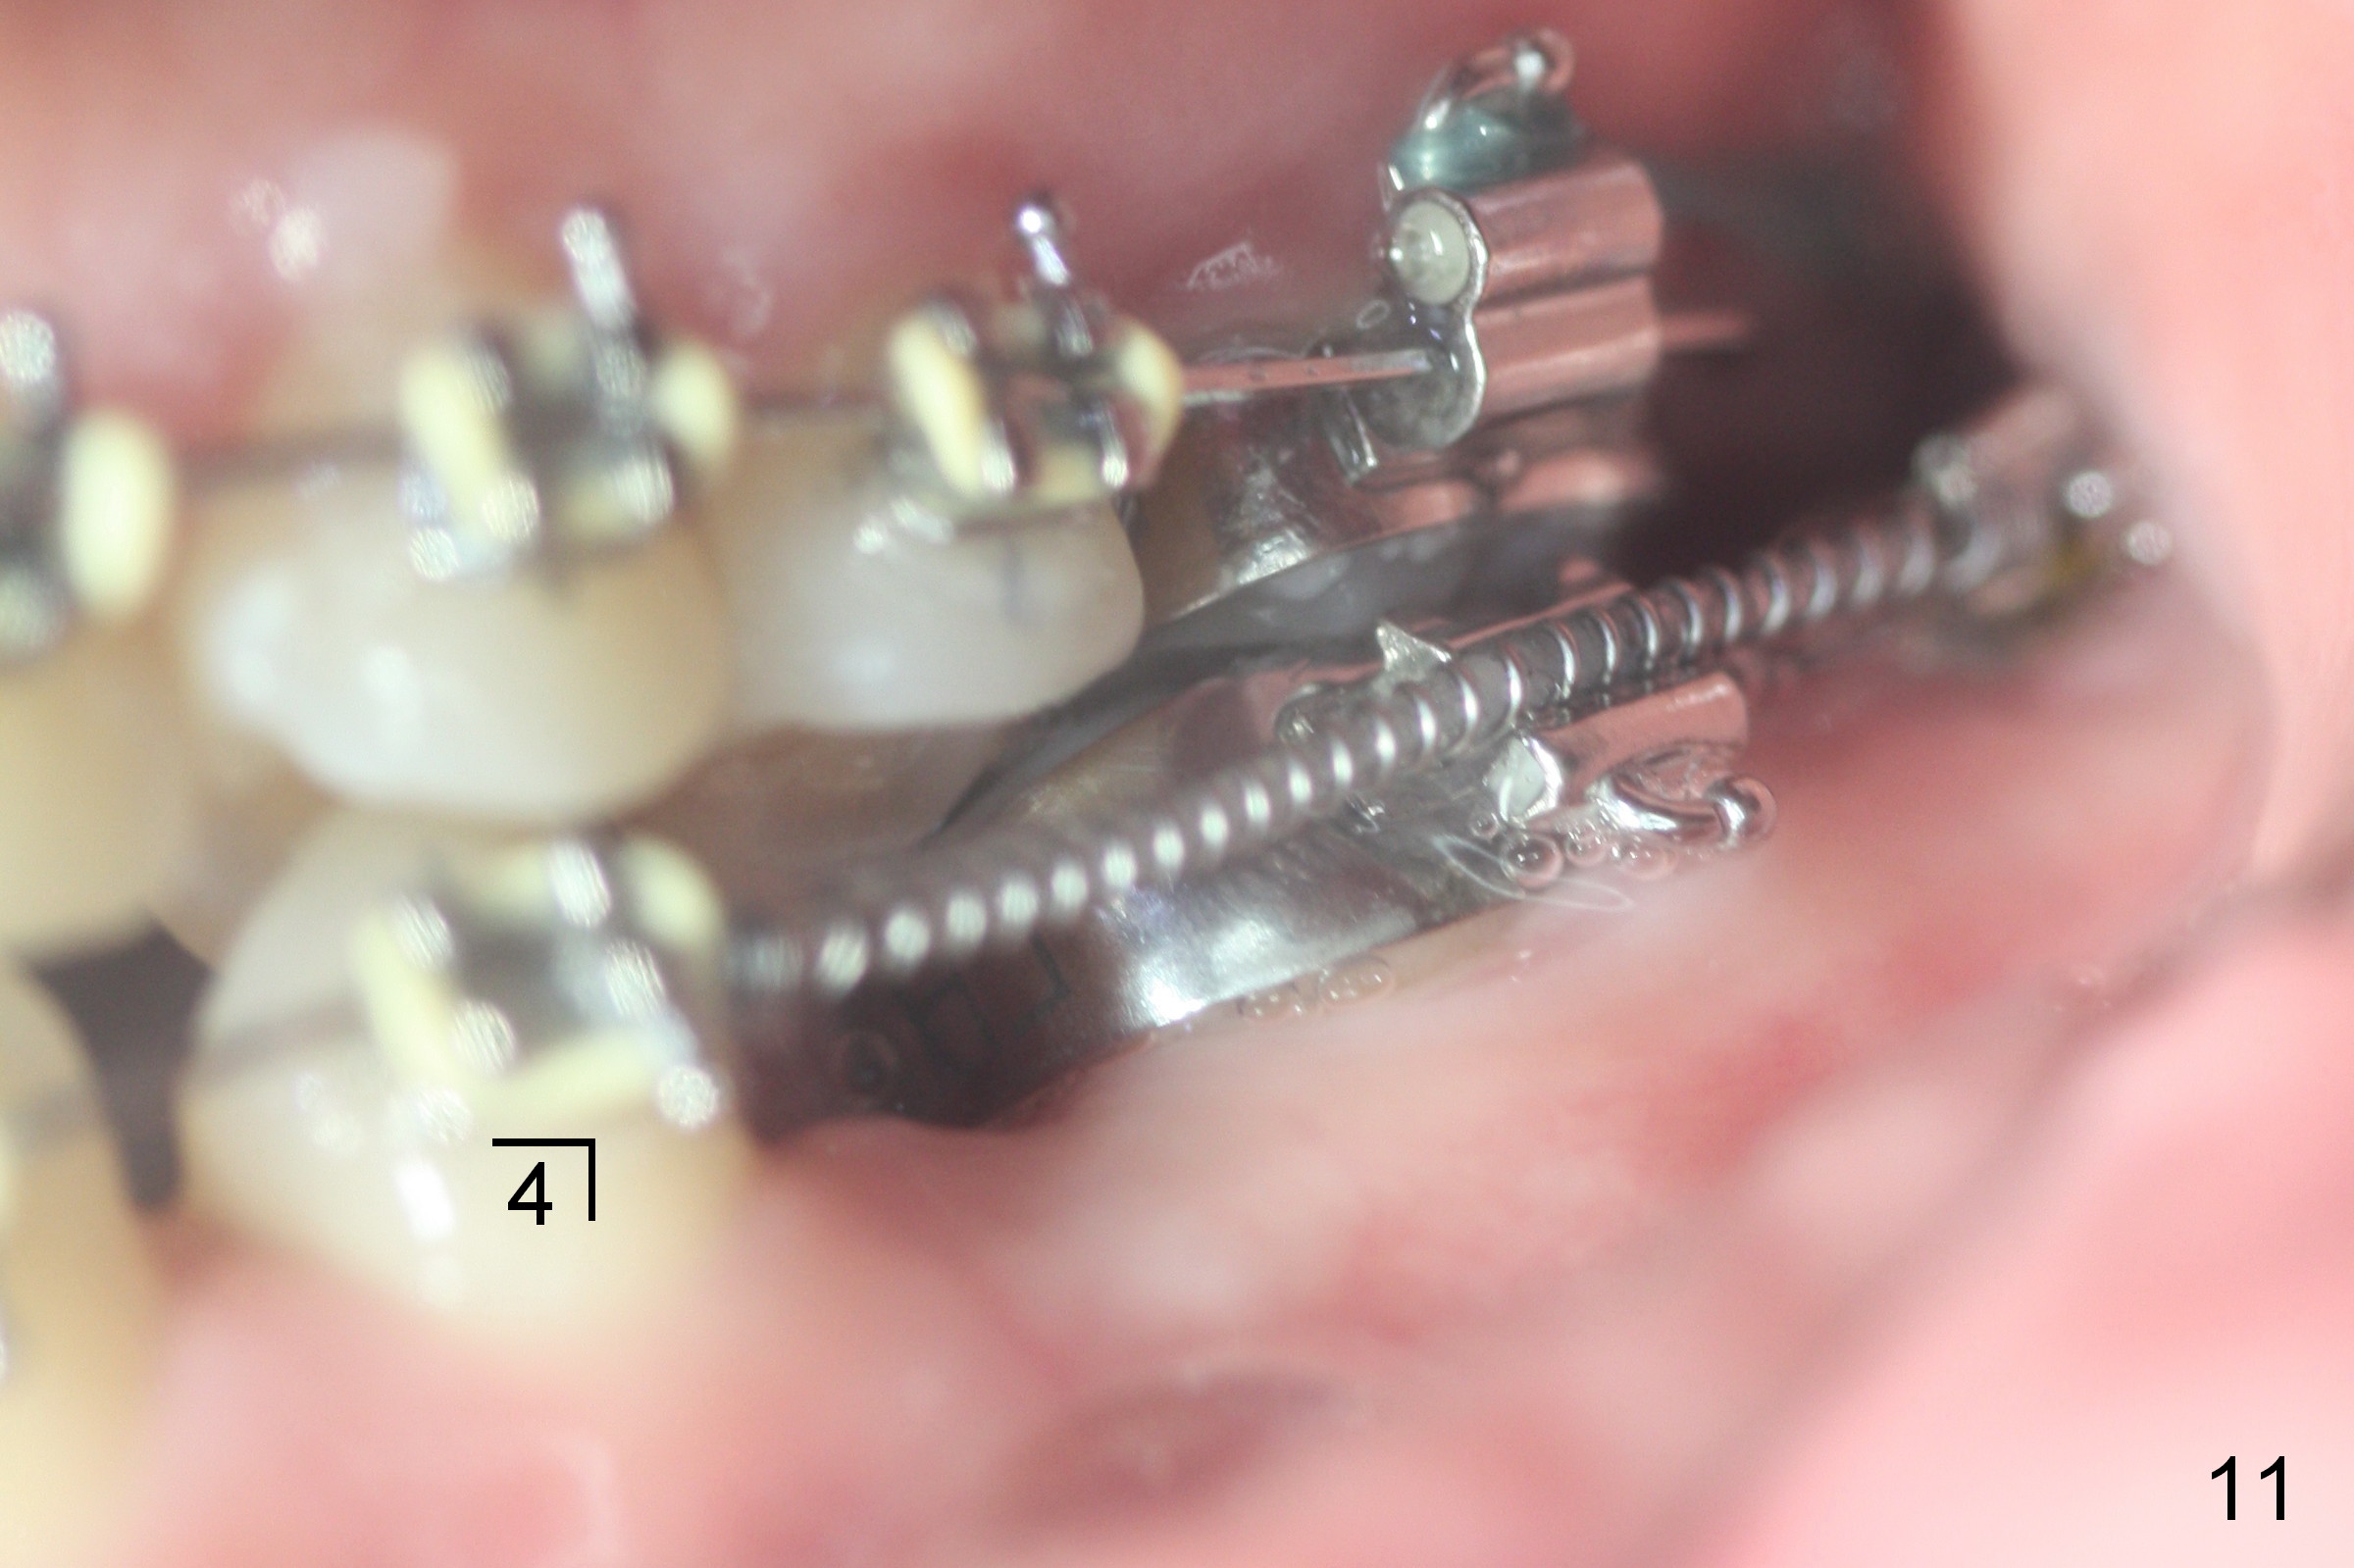

Four months post bracketing, two of 8 mm Ancor Mini-implants are placed at the sites of the upper 2nd molars and power chain of 3 placed between the 1st molars and the mini-implants (Fig.6,8). Niti Closing Springs (12 mm and 9 mm) are placed between LR4 and 7 and LL 3 and 6, respectively (Fig.7,9, 16x16 ss wires). The forces are 100 and 150 mg, respectively.

Two weeks later, it appears that U3s do not move distal (Fig.10,12), whereas the lower teeth do (Fig.11,13). Power chains change to 2 with grey ones. If no more change occurs in 1 week, change to next wires with power chains x 4 with one end attached to the lingual cleat (Fig.10,12 arrowheads) so that U3s may evenly (buccal and palatal) move distal. If LL3 keeps moving much faster than LR4, switch the closed coil springs.